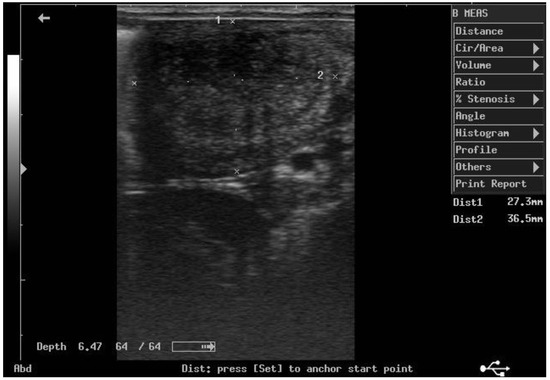

According to ultrasonographic records (Table 1), the mean T diameters did not differ significantly between PPH and NPPH at any time, whereas the mean M diameter of the PPH was larger than the NPPH only until PP Day 7 (Figure 1, Figure 2, Figure 3 and Figure 4). The Bonferroni post hoc test confirmed the ultrasonographic data obtained by ANOVA for repeated measures, when PPH and NPPH were considered across time. Moreover, when only time was assessed, the Bonferroni post hoc test highlighted similar significant changes occurring between PP Days 1–3 and 14–28 (p-value ranging between <0.05 and <0.001) and between PP Days 7 and 14–28 (p-value ranging between <0.05 and <0.01) for the M and CCJ. In relation to T, significant changes were detected among all the times of observation, with p-value ranging between <0.05 and <0.001.

Figure 2. Ultrasound image of the middle tract of the non-post-pregnant uterine horn, at day 7 postpartum.

The diameter of the CCJ in the PPH was not measurable until PP Day 3, then the mean diameter of the CCJ resulted larger in the PPH in comparison to NPPH only at PP Day 7. The first PP ovulation, detected by ultrasonography, occurred 11.9 ± 1.3 days after foaling. At the first PP ovulation, the follicle diameter was 45.1 ± 2.8 mm.